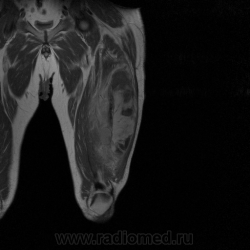

Ну вот аксиальные срезы, где то затерял =(

С учетом вашего опыта, мне кажется Вам и без дословной интерпретации МР-протокола будет все понятно.

Мой коллега в заключении указал о вероятней всего рабдолейомиосаркоме, если я ошибся то чуть позже поправлюсь.

Я тоже пока что в этом деле лось, но думаю дело поправимое, на днях улетаю С-Петербуг в МАПО(цикл КТ и МРТ), ну да ладно, что косается пациента то он ещё в 2007 году обращался по месту жительства к травматологу по поводу ушиба бедра с формированием гематомы, была назначена местная рассасывающая терапия, до 2009г. видимо ждали пока рассасется в декабре обратился к хирургу по поводу посинения и увеличения в объёме задней поверхности бедра, назначен гепарин в феврале был вскрыт абсцесс в этом месте, далее только в марте сподхватились по УЗИ-мягких тканей признаки образования, ну и открытая ножевая биопсия: Описание изменений, выявленных при микроскопическом исследовании: в материале фрагменты опухоли, представленной пучками вытянутых клеток с полиморфными гиперхромными, местами уродливыми ядрами. Определяется значительное количество митозов, встречаются поля некроза опухоли. При иммуногистохимическом исследовании опухолевые клетки экспрессируют виментин, отсутствует реакция на десмин, гладко-мышечный актин, S100. Патоморфологическое заключение: саркома мягких тканей, боее вероятно фибросаркома.